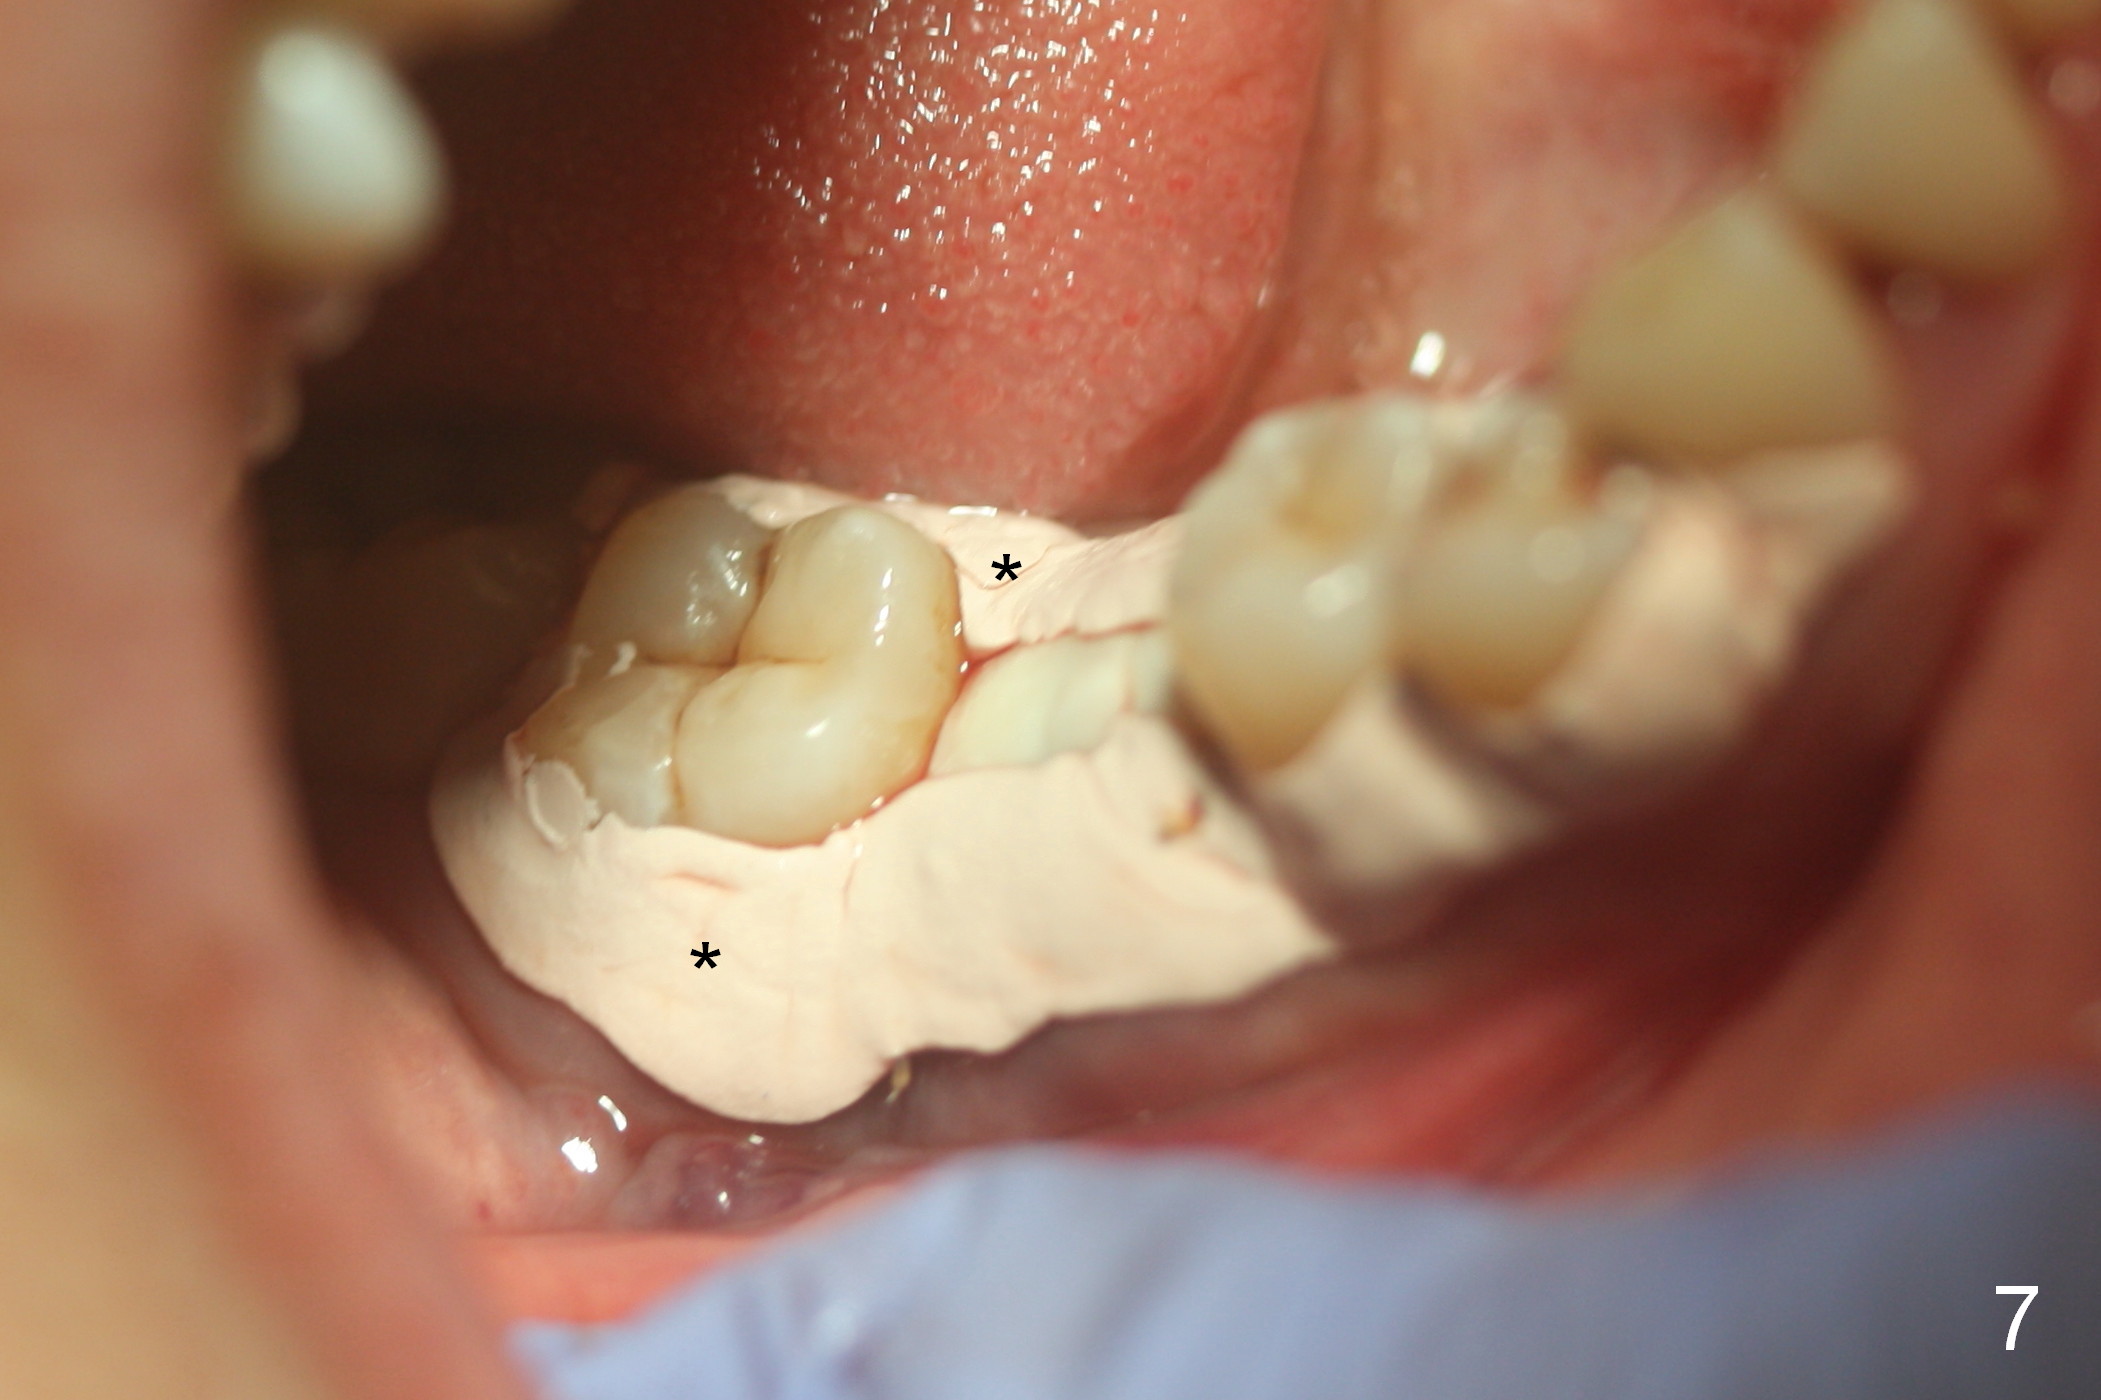

After cleaning the root surface with a surgical curette, a 1.6 mm pilot drill is used to start osteotomy (O) between the mesial (M) and distal (D) roots, followed by a marking bur and 3.8 mm Magic drill 13 mm deep (Fig.1,2). Following root removal, the 3.8 mm drill is reused for 11 mm (Fig.3). After deepening the osteotomy for another 2 mm, a 4.5x13 mm implant is placed with insertion torque of 50 Ncm, followed by allograft (*, .5-2 mm) and a 5x4(2) mm abutment (Fig.4,5). An immediate provisional is fabricated to close the socket (Fig.6 P (lock in)). The detached buccal gingiva (Fig.6 *) is kept in place by applying periodontal dressing (Fig.7 *). Red dashed lines in Fig.1, 3, 5 represents the superior border of the Inferior Alveolar Canal and Mental Foramen.